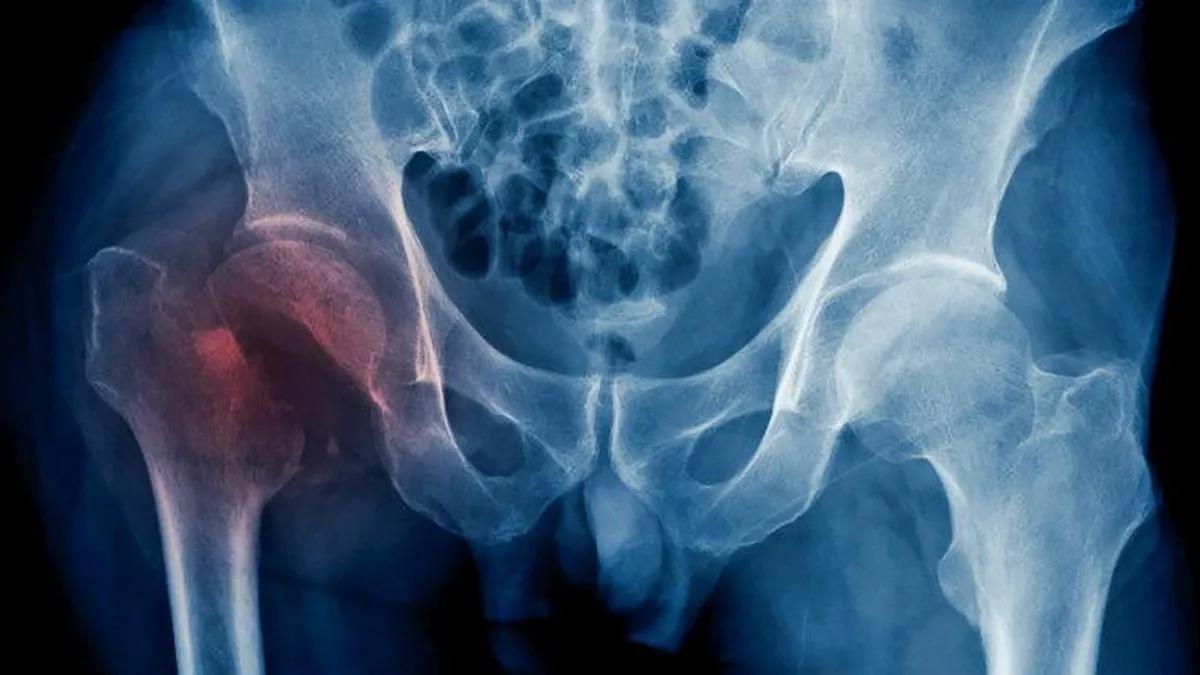

Otra quebradura frecuente es la de cadera. Esta es especialmente delicada debido a que presenta una alta morbilidad y mortalidad y se considera un acontecimiento grave ya que impide el movimiento por mucho tiempo y puede presentar complicaciones como coágulos sanguíneos en las piernas o los pulmones, escaras, que son lesiones en la piel y neumonía.

Esta afección requiere de intervención quirúrgica, ingreso hospitalario y supone para el paciente una pérdida de calidad de vida aunque sea por un periodo corto de tiempo. Otras localizaciones frecuentes de fractura son las vértebras dorsales y las lumbares.